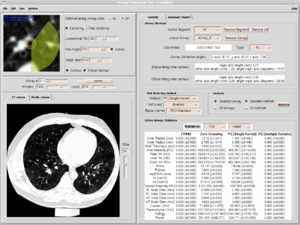

Publication: J Thorac Imaging. 2016 Jan;31(1):29-36. PMID: 26429588| PDF Authors: Zach JA, Williams A, Jou SS, Yagihashi K, Everett D, Hokanson JE, Stinson D, Lynch DA, COPDGene Investigators. Institution: Divisions of Radiology, Biostatistics and Bioinformatics, National Jewish Health, Denver, CO, USA. Background/Purpose: The purposes of this study were to evaluate the effect of smoking status on quantitative computed tomography CT measures of low-attenuation areas (LAAs) on inspiratory and expiratory CT and to provide a method of adjusting for this effect. Materials and Methods: A total of 6762 current and former smokers underwent spirometry and volumetric inspiratory and expiratory CT. Quantitative CT analysis was completed using open-source 3D Slicer software. Funding:

Examples of CN on CT. Coronal CT image of a GOLD 1 subject with moderately extensive visual extent of emphysema. However, the quantitative emphysema score was only 5.1%. The emphysema may have been masked on quantitative assessment by the presence of centrilobular nodules (circled) and patchy ground-glass abnormality (arrows). |